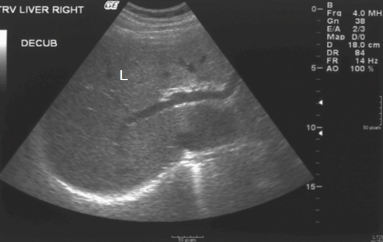

The liver contains two areas (arrows) that are ____________ compared with the rest of the echogenicity of the liver

hyperechoic